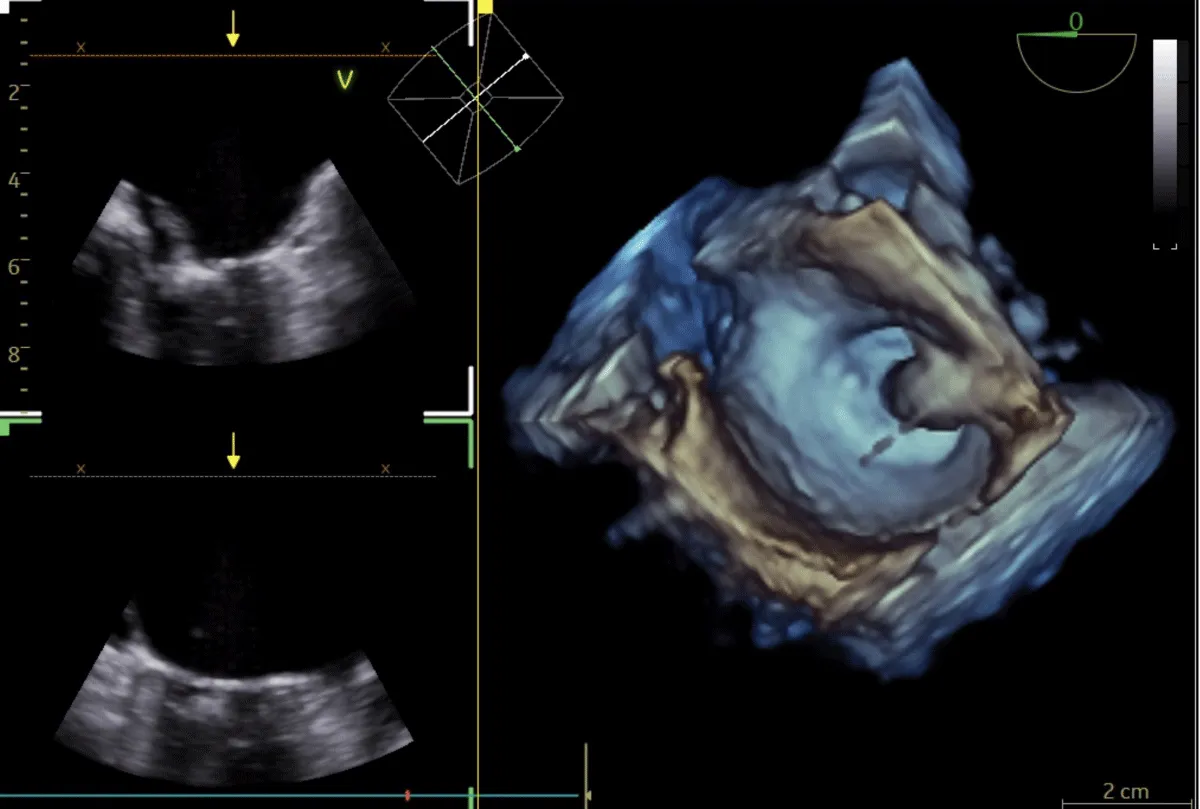

He was planned for double valve replacement (DVR), but the patient declined due to the high surgical risk. Therefore, he was considered for staged BMV and Transcatheter aortic valve replacement (TAVR). Pre-procedural planning was done for TAVR, and after ensuring the patency and adequacy of femoral vessels, he underwent a coronary angiogram (CAG), which showed normal coronaries. Following consent, the right femoral vein was accessed. A transseptal puncture was performed with a broken Brough needle, and the LA wire was parked. The MV was dilated with a 26 mm Inoue balloon (Figure 7), resulting in a reduction of the MV gradient from 24/10 mm Hg to 9/5 mm Hg and an increase in MV area from 0.9 cm2 to 1.6 cm2. There were no post-procedural complications. After 1 month, he underwent TAVI. Both right and left femoral artery access was obtained. Following pre-dilatation of the AV with an 18 mm balloon, TAVR was performed using a 26 mm balloon-expandable valve (Myval, Meril Lifesciences, Vapi, Gujarat, India) (Figure 8) (Video 3), followed by post-dilatation under accelerated right ventricular pacing (180 bpm). ECHO and final aortography showed no paravalvular leakage after device release (Figure 9).

Figure 9: Fluoroscopic image of aortic valve implantation without coronary compression after (A) and before the deployment (B).

Post-TAVR, the AV gradient was reduced from 98 →10 mm Hg. No procedural or post-procedural complications occurred. The hospital course was uncomplicated, and the patient was discharged after 4 days.